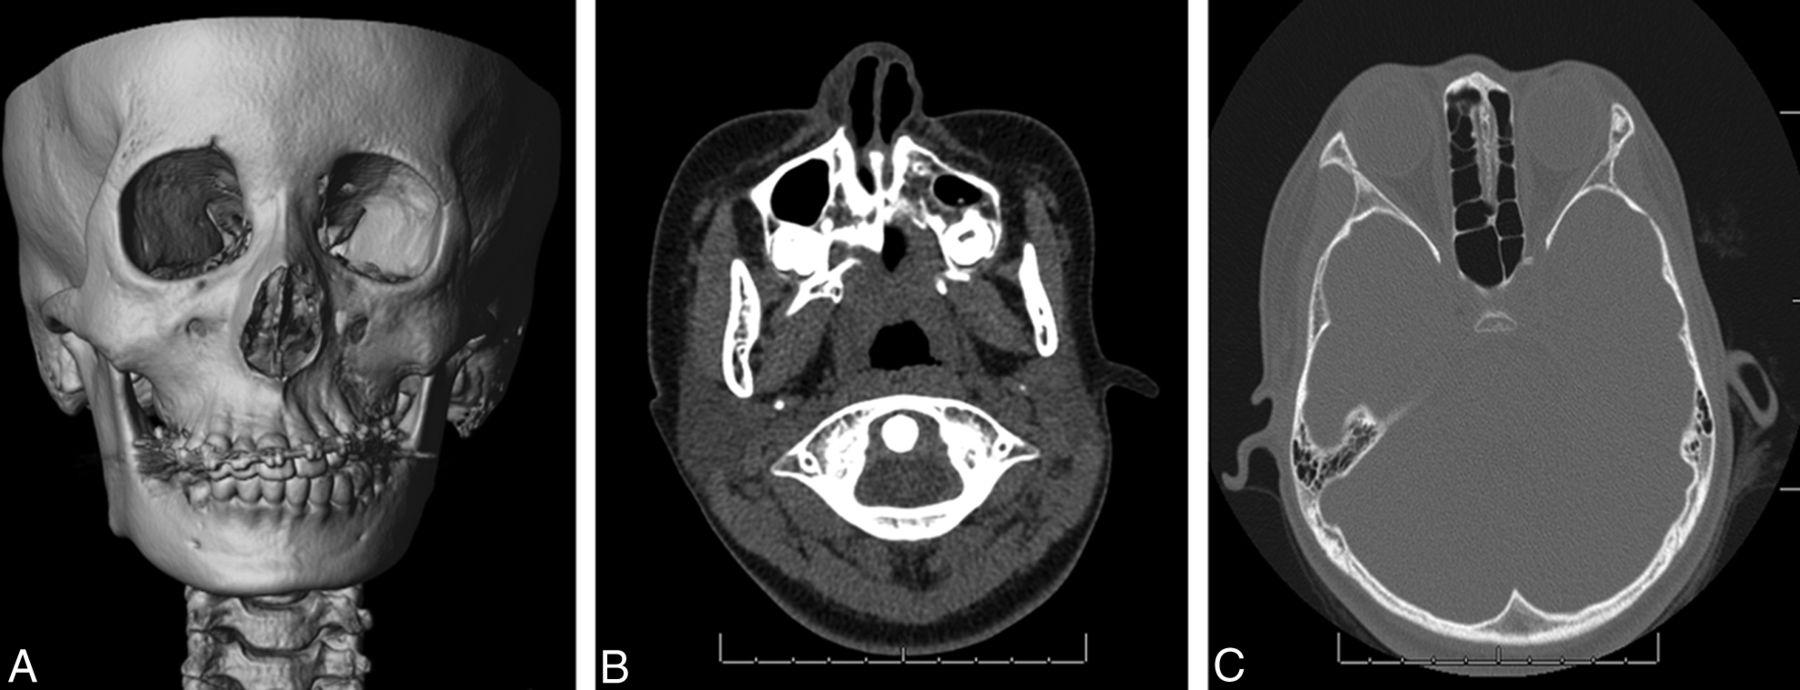

The Parry Romberg Syndrome Market industry is experiencing a critical shift driven by escalating R&D investments in biologic therapies and diagnostic imaging. With industry size expanding beyond historical expectations and industry share gravitating towards novel regenerative modalities, detailed market analysis underscores accelerating business growth. Current market dynamics and market drivers point to a competitive landscape focused on high-value orphan drug development.

Market Size and Overview

The Parry Romberg syndrome market is estimated to be valued at USD 455.8 Mn in 2025 and is expected to reach USD 827.9 Mn by 2032, growing at a compound annual growth rate (CAGR) of 8.9% from 2025 to 2032.

According to the Parry Romberg Syndrome Market report released in Q1 2025, biologic therapeutics and diagnostic imaging segments account for over 40% of Parry Romberg Syndrome Market revenue in 2024, driven by immunomodulators and stem cell interventions. Market trends in targeted gene therapy and advanced imaging are unlocking substantial market opportunities, while reimbursement gaps present notable market challenges. Annual capacity expansions and new labeling approvals are projected to bolster overall market size through 2030. The Parry Romberg Syndrome Market trends underscore a shift towards integrated therapeutic platforms and precision diagnostics by 2027.

• Late 2024 saw a Phase II trial by Novartis using adipose-derived stem cell injections at the Mayo Clinic, achieving a 30% improvement in facial volume and validating a key Parry Romberg Syndrome Market share shift toward regenerative medicine. Recent market research and market insights reveal such outcomes reinforce targeted cell therapy pipelines.

• In Q1 2025, Roche deployed its AI-based diagnostic imaging suite across three Paris hospitals, reducing diagnostic turnaround by 20% and illustrating market growth strategies for precision diagnostics in rare facial atrophy cases.